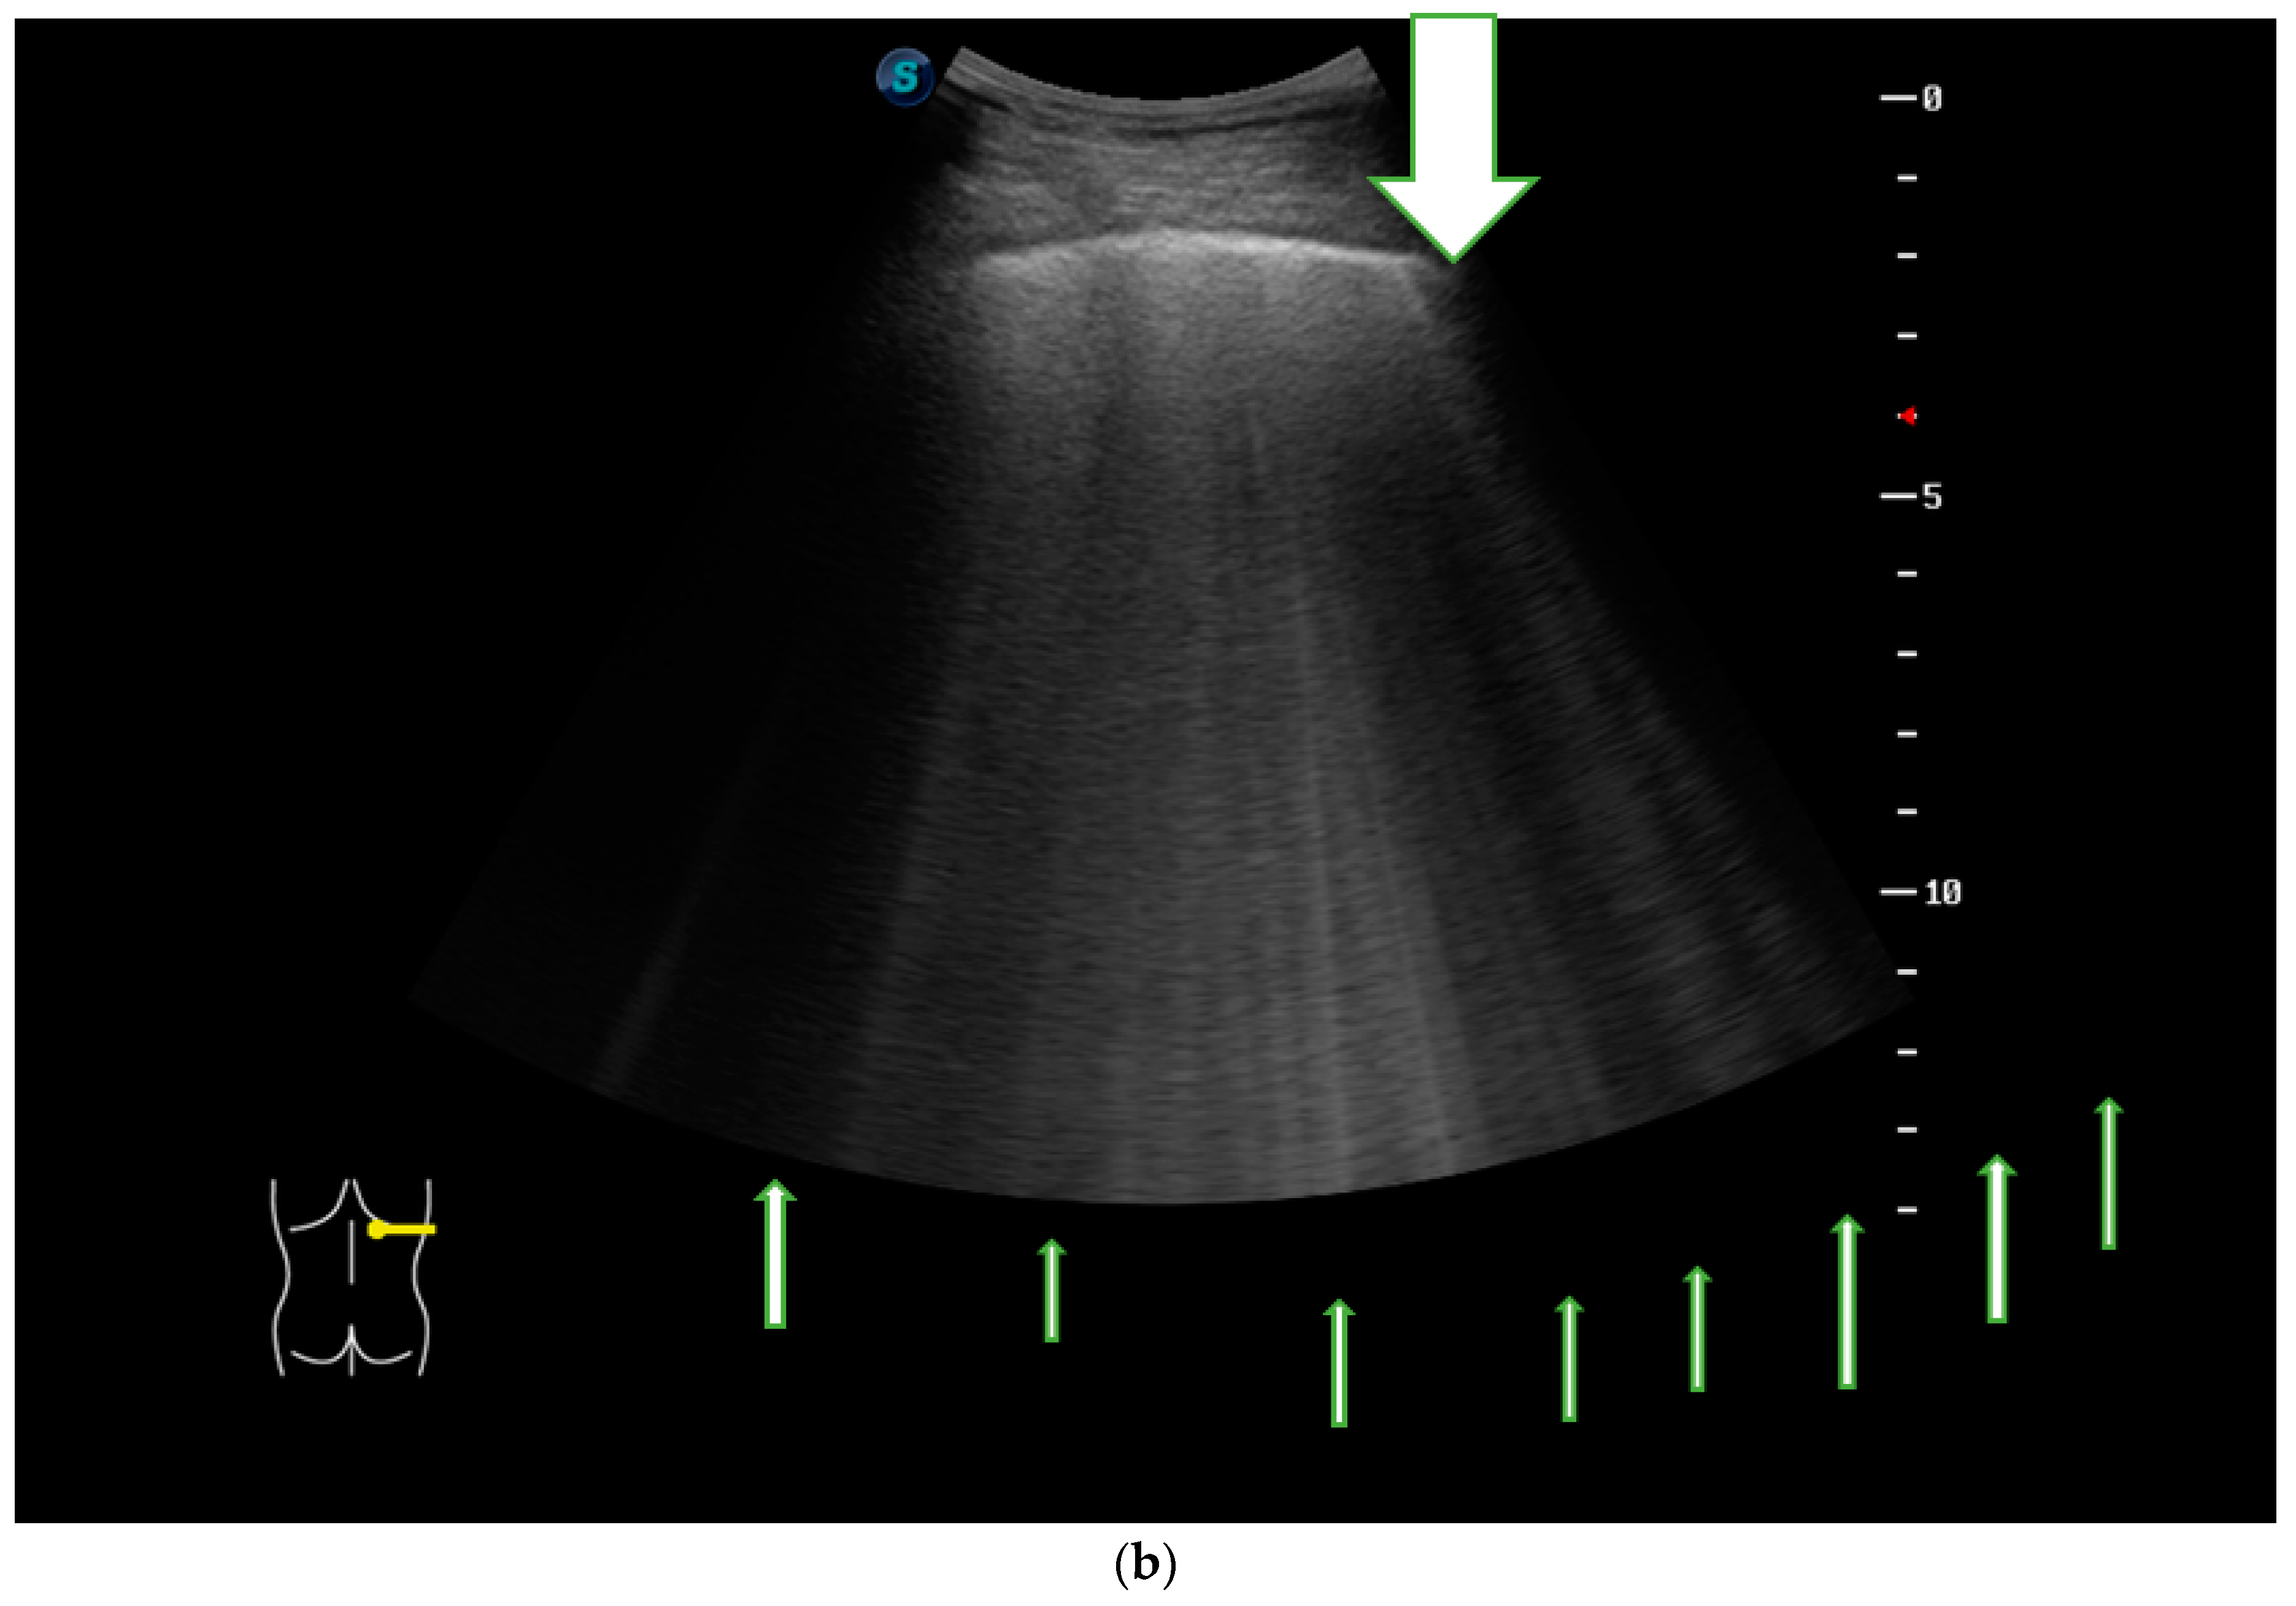

2.5. LUS Assessment and Quantification